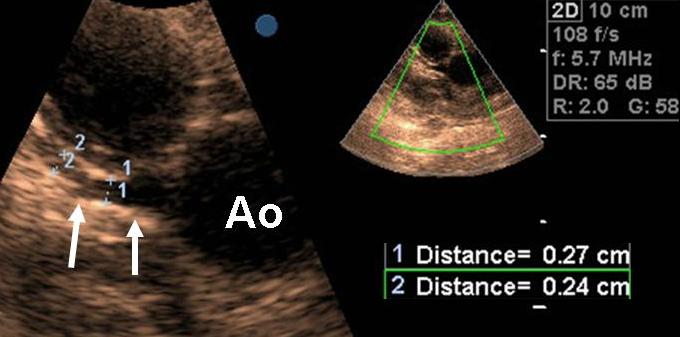

Ecocardiografiacolor-Doppler � tra le indagini strumentali pi�

la valutazione delle sequele (dimensioni delle camere cardiache,

efficacia della funzione di pompa ventricolare, asinergie di

contrazione del ventricolo sinistro, disfunzione diastolica,

dilatazione coronarica, etc; Figura 3), e la

Figura

3. Immagine ecocardiografica, proiezione parasternale asse lungo,

modificata. � ben visibile il tronco comune di coronaria

sinistra, dall�origine aortica alla biforcazione in arteria

discendente anteriore e in arteria circonflessa. Ao, aorta.